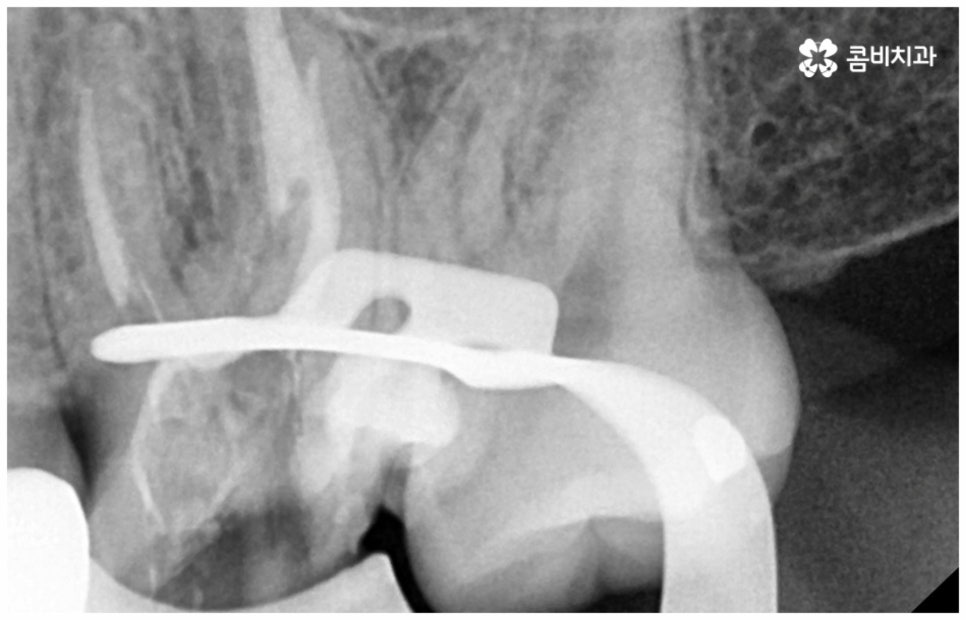

또한 어금니 신경치료를 할 때 러버댐 장착은 필수적인데요 (사진에서 볼 수 있는 하얀막), 이와 같이 고무막으로 치료할 치아만 빼고 나머지는 격리시키는 이유는 해당 부위로 침이 유입되는 것을 막고 최대한 습기를 예방하여 (방습법) 치료의 효율성과 치과 재료 기능을 향상시키는 것, 환자와 시술자간 교차 감염을 막아 오염 확률을 낮추는 것, 신경 치료할 때 쓰이는 약제 또는 치아 삭제시 생기는 찌꺼기 등이 입 안으로 흘러 들어가는 현상을 방지하는 것 등등 환자분들을 보호하고 치료의 질을 높이기 위한 목적이니 안쪽 치아라서 조금 불편하시더라도 필요성에 대해서 잘 인지하시길 바라고 있어요.